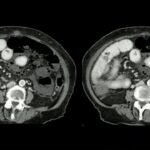

Esta medicação tem um mecanismo de ação bastante específico, diferente dos Anti-TNFs como Infecção Adalimumabe e diferente dos das Antes Integrinas como o Vedolizumab. O Estelar bloqueia um momento da cascata inflamatória do processo inflamatório, gerando bloqueio de vários marcadores inflamatórios, o que diminui a reação a nível da mucosa intestinal, diminuindo as lesões tanto da retocolite quanto da doença de Crohn.

E agora, a novidade que eu gostaria de compartilhar com os senhores é que tínhamos até então trabalhos do Estelar na doença de Crohn que foram bastante significativos com a efetividade bastante grande nos pacientes que apresentam doença de Crohn. Entretanto, os últimos trabalhos trazem a novidade de que o Estelar é efetivo também na reta politi, e já disse a novidade que ele é um corinthians seletivo, tornando-se mais uma alternativa para os nossos pacientes no controle desta doença.